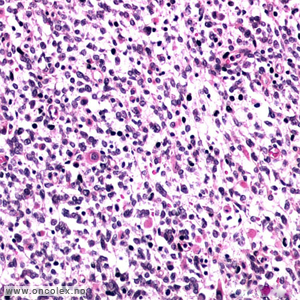

Ondartet embryonal neoplasme som utgår fra nefrogene blastemale celler. Det er en sammensatt svulst med en sammensetning av ulike celletyper. Blastemal epitelial  og stroma komponent. Blastemal komponent viser små umodne celler med minimal differensiering, overlapping av kjerner, ofte med flere mitoser.

Epitelial komponent kan vise tubuli, primitive rosetter eller etterligne umodne glomeruli.

Stromakomponent kan bestå av spolformete myofibroblaster over myxoid cellefattig vev, til tverrstripet muskulatur. Sammensatte komponenter (brusk, fett, osteoid, neuroglia) er ikke uvanlig.